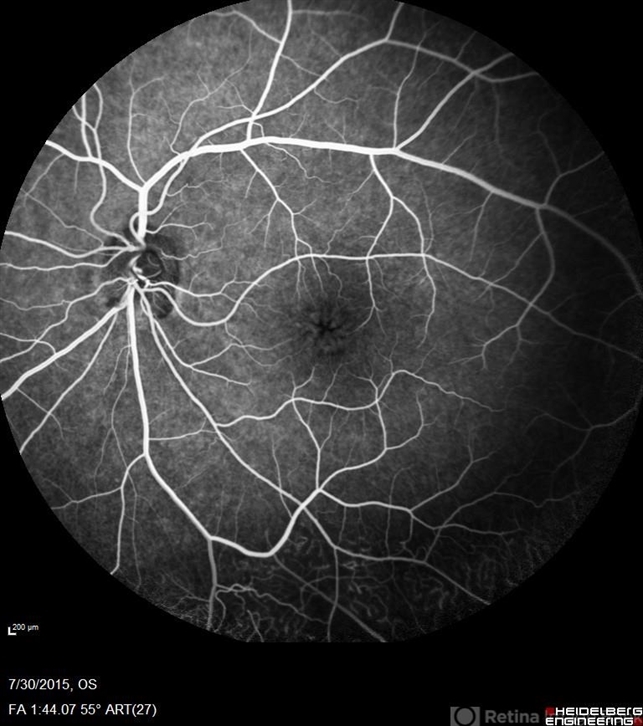

- retinal dystrophy, Goldmann-Favre Syndrome, juvenile retinoschisis

- Fluorescein angiography of a 24-year-old male. Juvenile retinoschisis on OCT. FA shows outer retinal staining. Could be associated with Goldman Farve Syndrome.